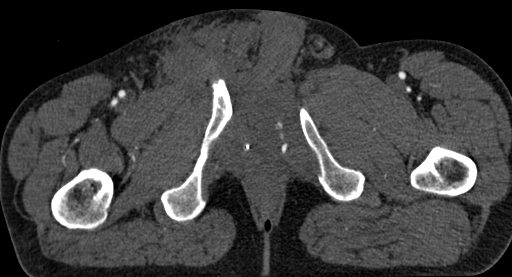

Im Schockraum-CT (Polytraumaspirale) zeigte sich neben einer vorderen und hinteren Beckenringfraktur auch eine akute Blutung im kleinen Becken durch eine Ruptur der linken A. pudenda interna (Abb. 1 und 2).

Abb. 1 früharterielle KM-Phase

Abb. 2 spätvenöse KM-Phase